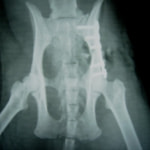

症例3:キルシュナーワイヤーのピンニングによる整復

ペルシャ猫 11ヶ月齢 雄

他院にて左大腿骨遠位の成長板骨折(salter-harrisⅠ型)が認められており、治療相談を目的として来院。当院にて、キルシュナーワイヤーを用いたピンニングにより骨折部位の整復を行いました。術後の経過は良好で、現在も経過観察中です。

術前レントゲン